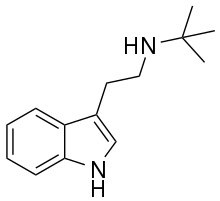

| Tryptamine | Animals, plants, fungi | H | H | H | 3-(2-aminoethyl)indole / 2-(1H-indol-3-yl)ethanamine | 61-54-1 |

| NTBT | artificial | H | H | C(CH3)3 | N-[2-(1H-indol-3-yl)ethyl]-2-methylpropan-2-amine | |